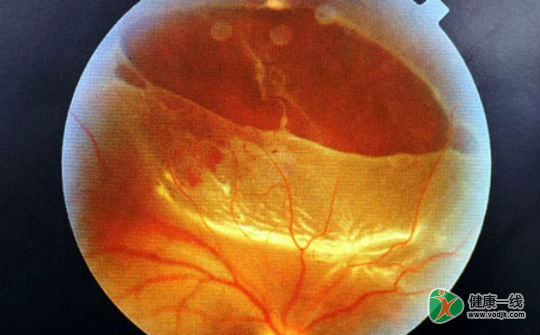

视网膜脱落症状图片

视网膜脱落的症状主要还是要看视网膜脱离的具体位置和范围。如果脱离的位置不重要,范围不大的话,患者有可能没有任何症状。相反,如果正好脱离在眼球的后极部,而且范围比较大的话,患者的视力有可能会接近于完全丧失。

视网膜脱离的主要症状 1.网脱发生前常出现火花与闪光幻觉。 2.有时感到眼前有一层乌云般的黑影从一个方面朝着视野的中央部推进。 3.视物模糊、视物变形。 4.

视网膜脱落的早期症状有哪些?视网膜脱落严重吗?有问必答网视网膜脱落疾病查询频道为您解答视网膜脱落的症状知识,当视网膜发生部分脱离时,病人在脱离对侧的视野中出现